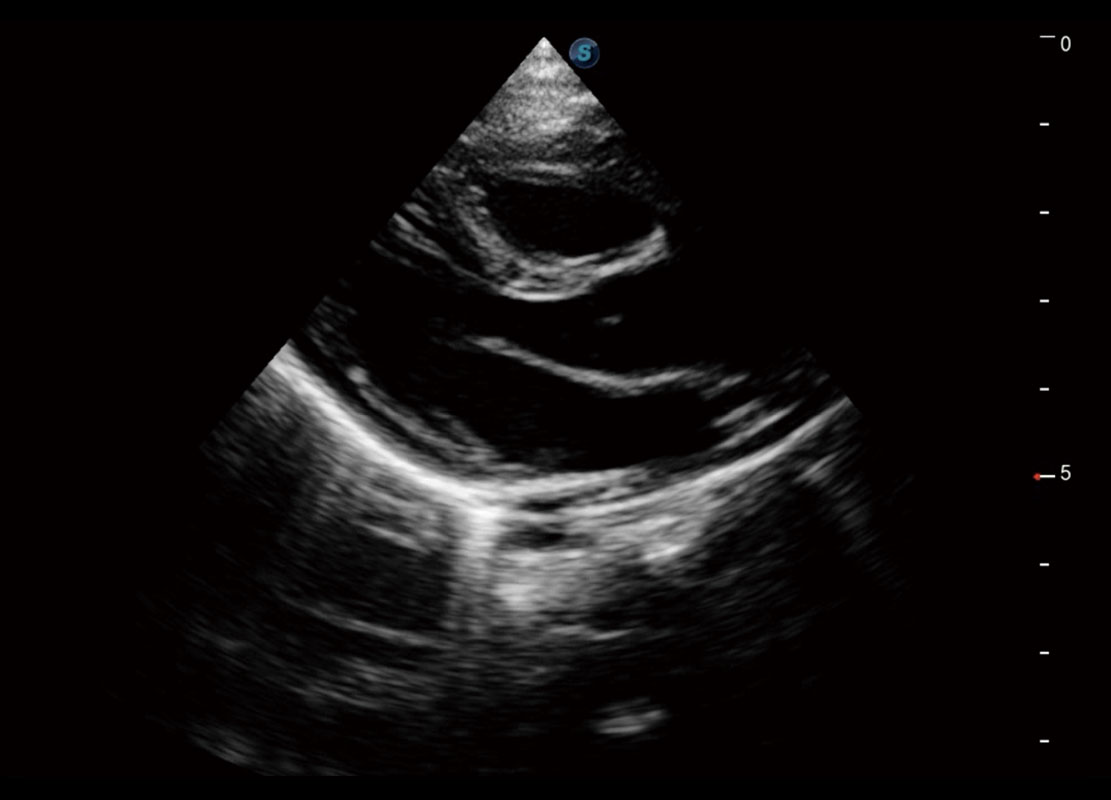

胎心筛查

P60搭载一系列胎儿心脏成像技术,实现精细的胎儿心脏评估。

• 四腔切面

• 四腔心血流